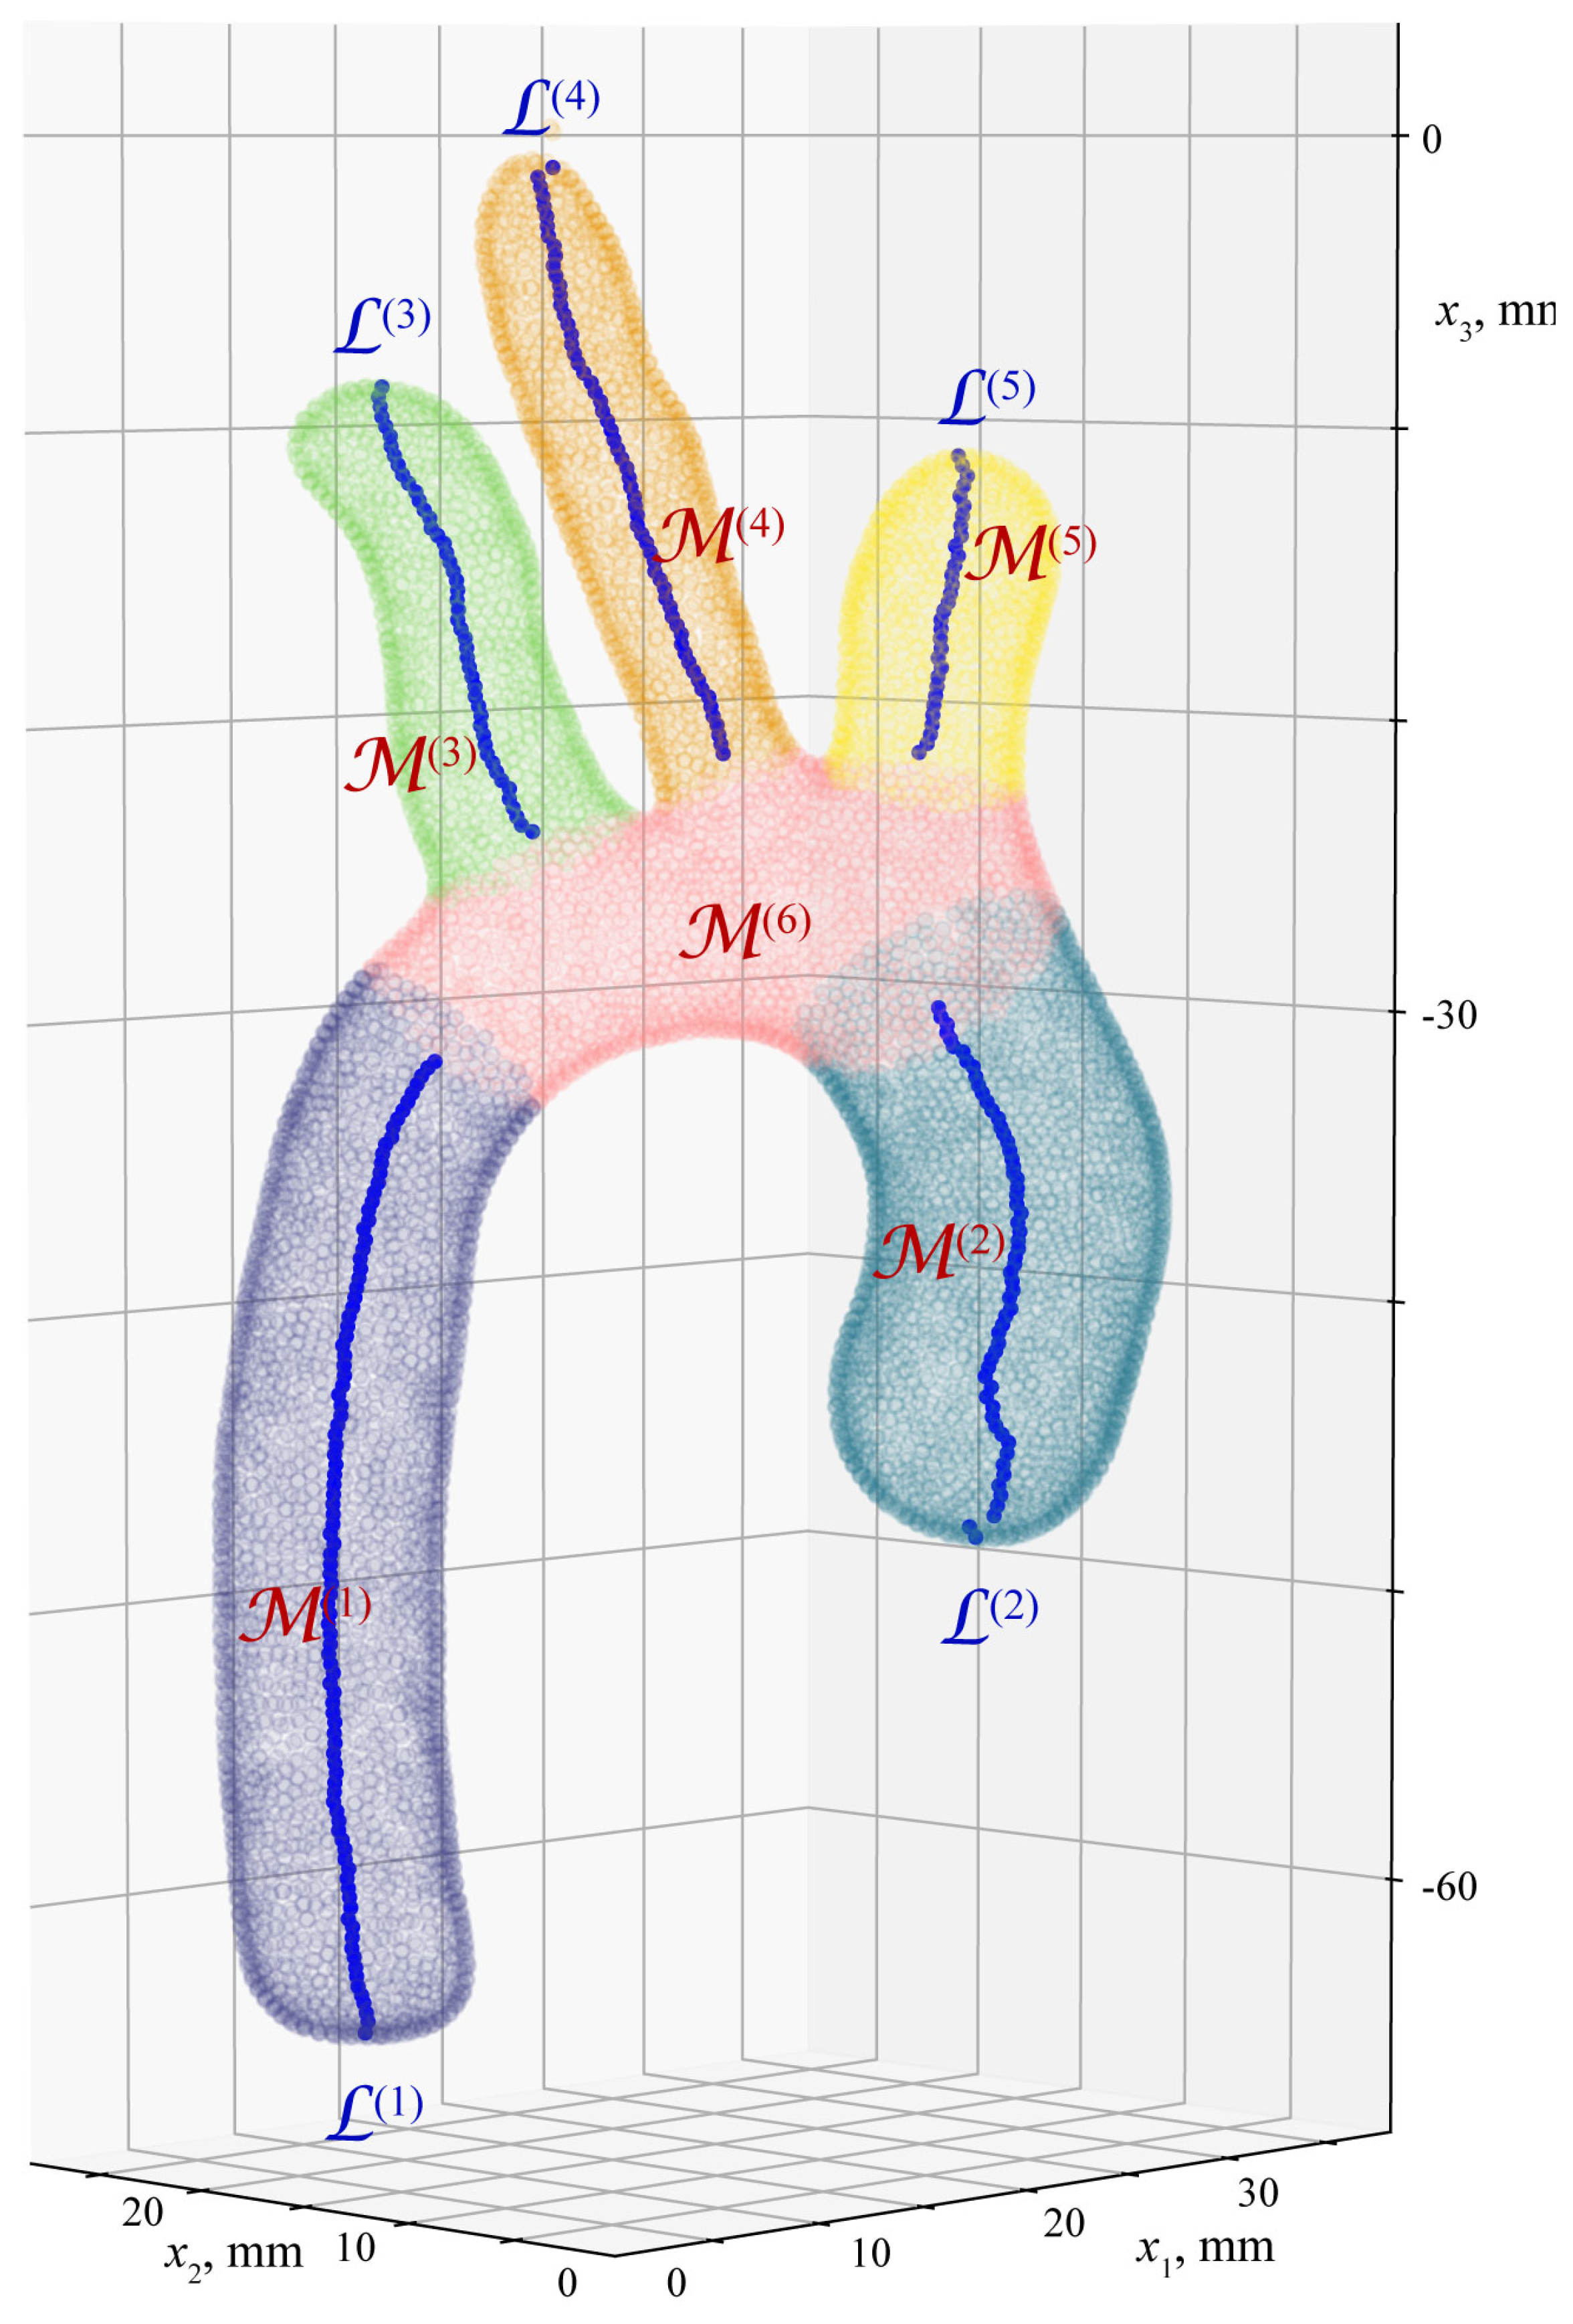

4. Algorithm for Extraction of Geometrical Characteristics of Aorta